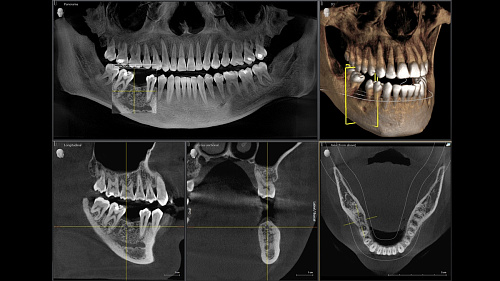

При помощи такого оборудования специалист сможет успешно решить широкий спектр диагностических и лечебных задач. Качественное изображение, достоверность при разноуровневой резкости (технология Sharp Layer), гибкий объём, 30 доступных вариантов цвета. Цефалометрическая визуализация позволяет получать боковые или симметричные снимки, а также определить положение при смещении зуба. Работая при разрешении до 80 мкм в режиме низкой дозы и HD, вы получаете качественные изображения выбранного формата, заботясь о комфорте и безопасности пациента.

Диагностика последнего поколения, идеально решающая задачи рентгеновского обследования независимо от размеров клиники. Поля изображения зависят от определенной клинической картины, поэтому специалистам так удобно работать с ORTHOPHOS SL 3D. Данная установка делает объёмные картинки для одиночной реставрации в 3D качестве полностью всей челюсти такого размера, которого требуется.

Планирование одиночной реставрации, эндодонтические исследования и пр. – для этого специалист может выбрать объёмные варианты 8 х 8 см или 11 х 10 см, также предлагается объём 5 х 5,5 см. Снимки в HD-качестве, стандартные настройки или выбор объёма обследования в зависимости от диагноза — всё это врач получает в отличном качестве, а для пациента излучение в районе исследования минимально.

Конструктивные особенности датчика DCS заключаются в превращении рентгеновского излучения в электрическую энергию. Обычная для таких случаев промежуточная стадия светового луча отсутствует. Другими словами, значительно снизив потери сигнала, производитель максимально улучшил чёткость.

С технологией SL можно за один сеанс получить огромное количество снимков. Те из них, где фокусировка наиболее чёткая, автоматически соединяются. В итоге одна процедура — снимки челюсти полностью в самом лучшем качестве. Даже нестандартные случаи не станут помехой в обследовании. К примеру, при ретинированных зубах уже после того, как снимок сделан, нужную область можно выделить подробнее, и в ещё одном рентгене необходимость отпадает.

Металлические элементы в ротовой полости могут привести к возникновению помех на снимке. Благодаря наличию программного обеспечения MARS наличие объектов из металла определяется автоматически, влияние артефактов нивелируется. Таким образом не требуется повторного изображения для уточнения диагноза.